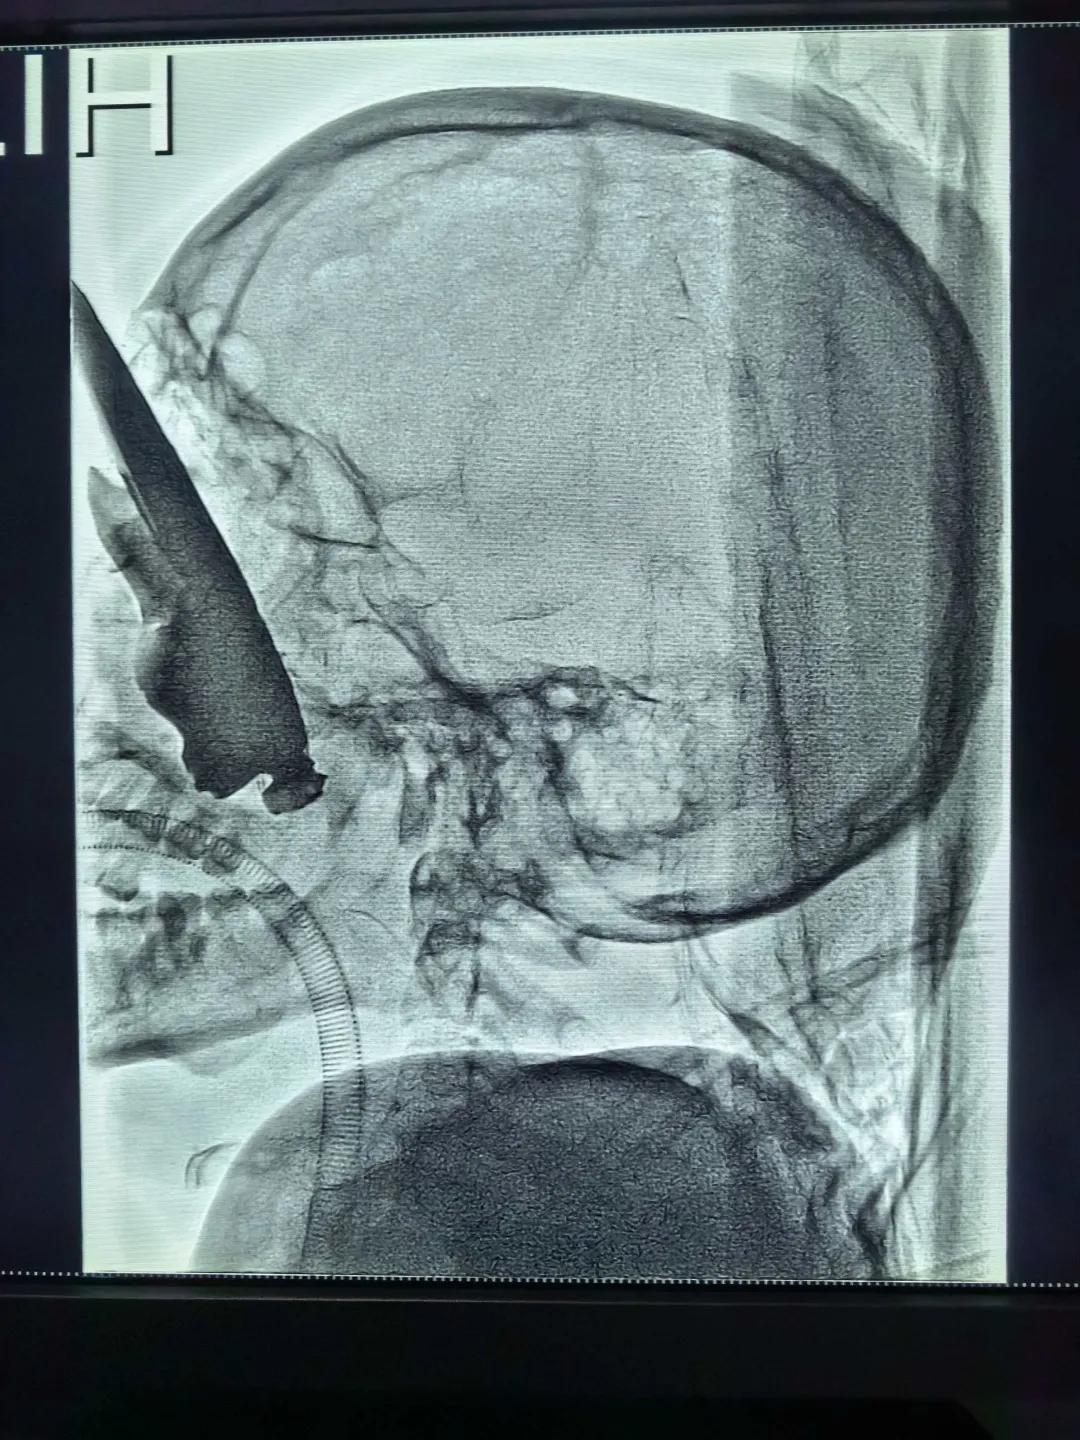

2月26日凌晨4:30,刚结束前一日手术的杨夏接到紧急电话:一名24岁男性患者因右侧眼眶贯穿伤,异物经眼眶进入颅内,穿透鼻腔、鼻骨,横贯右侧颌面部及口底至左侧上颌骨,出血量大,生命垂危。

杨夏立即赶回医院。神经外科先行血管造影后,神经外科、眼科、口腔颌面外科等多学科团队迅速制定手术方案,成功取出一根长达19cm、宽近7cm、厚4cm的巨大金属异物。因右眼球毁损严重,眼科行眼球摘除及眼窝成形术;神经外科同期行颅底修补及脑脊液漏修补;口腔颌面外科及五官科接力完成清创修复。术后患者生命体征平稳,左眼及视力成功保住。

一名24岁男性患者因右侧眼眶被异物贯穿,经额部进入颅内,并穿透右侧鼻腔、鼻骨,横贯右侧颌面部及口底,直达左侧上颌骨,生命垂危,出血不止。患者被收入颅脑外科,急需眼眶专科等多学科联手抢救。

CT显示,右侧眼眶被异物贯穿,并穿透右侧鼻腔、鼻骨。

疲惫瞬间被驱散,杨夏火速赶回医院。同样在介入手术保障下,先行血管造影评估风险,随后与颅脑外科医生并肩作战。在全麻下,一个令人震惊的金属异物被取出:最长处达19厘米,最宽处近7厘米,最厚处4厘米,形同一把恐怖的“金属扫帚”。